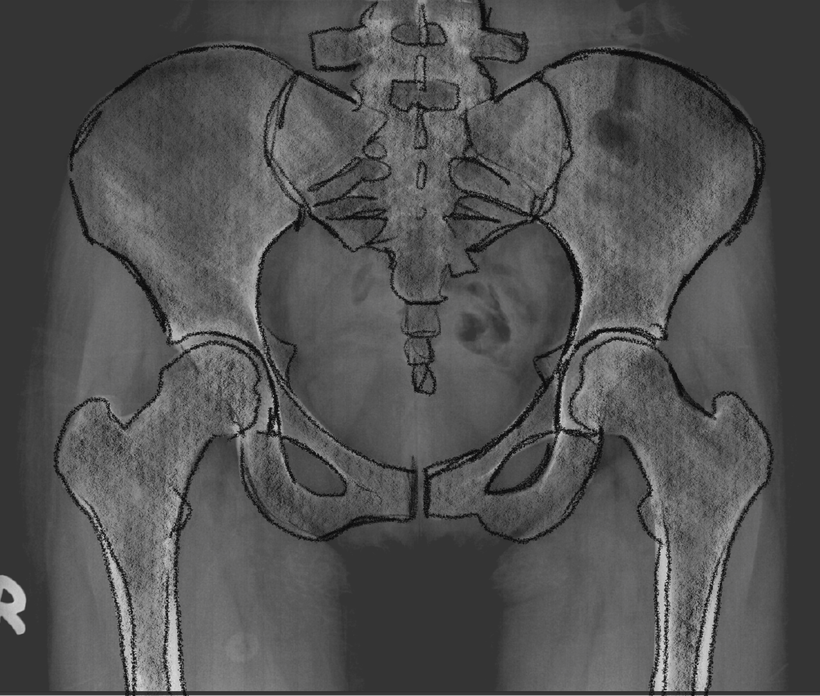

Orthopaedic Surgeon

Precision meets personality

Hamish McLaren needed a digital presence to match his expertise in robotic joint replacement. We designed a sleek, patient-friendly site paired with brand photography that captures his calm confidence and cutting-edge care.